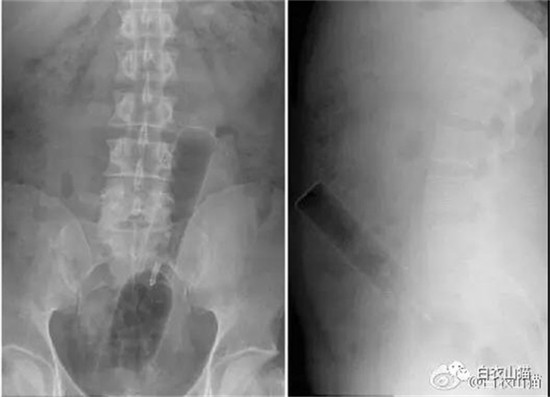

这是一个啤酒瓶。男性。

上面是一个啤酒瓶在大肠里。病人是男性。这是常见的肛门内异物。

这种情况,往往只要给病人打上全身麻醉,肛门松弛后,就可以用卵圆钳经过肛门把啤酒瓶拉出来。